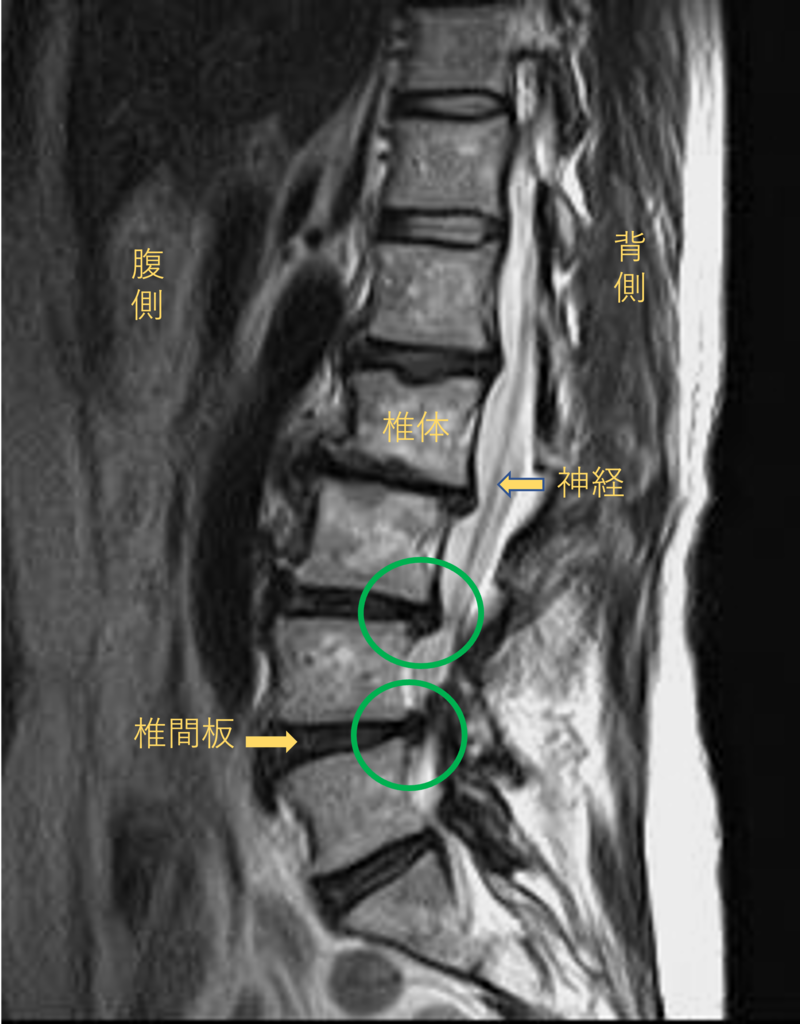

腰を横から見たMRI画像です。

腰椎という骨と骨の間に椎間板と呼ばれるクッションがあります。

このクッションの中身が飛び出す状態が椎間板ヘルニアと呼ばれます。

このMRI画像では、椎間板が背中側に飛び出して足に向かう神経が圧迫されることが痛み、しびれの原因となっておりました。